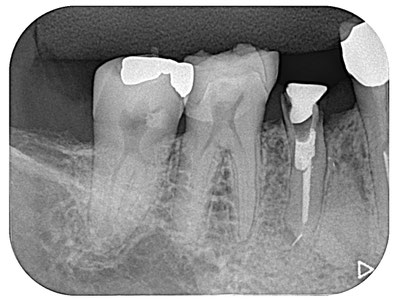

他院で抜歯宣告された歯です。下の奥から3番目の第2小臼歯です。この歯には4つの問題点があります。

①治療用の器具が根の先で折れている(赤点線囲)

②根の先に病巣がある(黄点線囲)

③土台を入れるために歯を削ってありますが、その方向が本来の方向とは異なる方向に削られている。(緑点線囲)

④残っている自分の歯が歯肉の高さスレスレである(白点線囲)